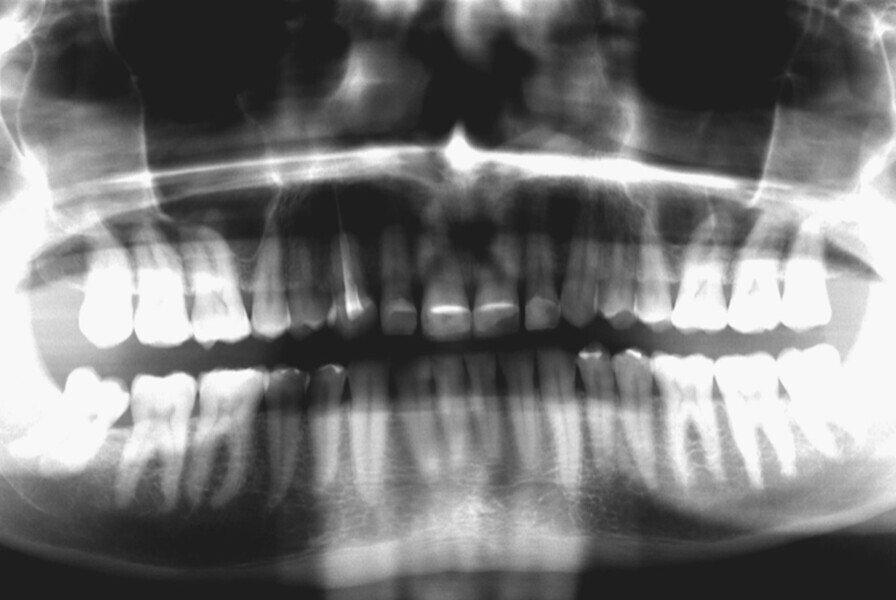

Fig. 15: Panoramic image at the end of treatment.